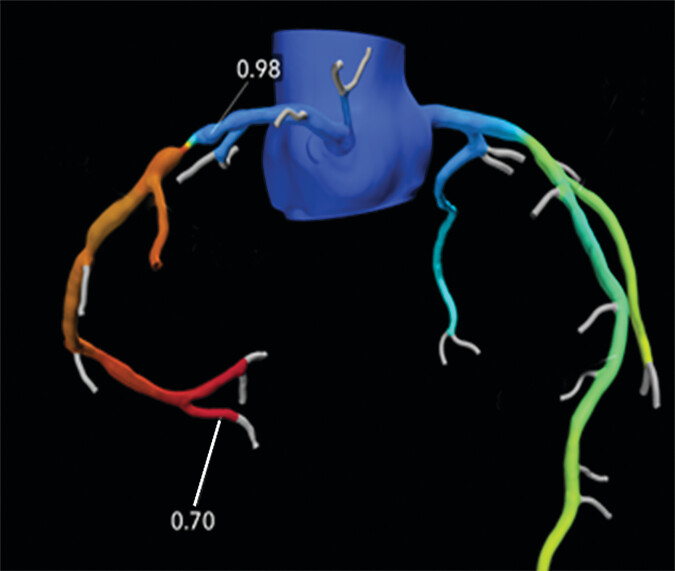

Méthode

L’approche combinée jumeau numérique CFD + IA permet une estimation rapide et précise de la FFRct à partir de simples maillages coronaires, réduisant considérablement le temps de calcul tout en conservant une haute précision. Elle ouvre la voie à une intégration clinique à grande échelle, y compris dans des environnements contraints en temps ou en ressources.

Cette étude propose une approche hybride combinant un jumeau numérique CFD haute fidélité et un modèle d’intelligence artificielle pour estimer rapidement et avec précision la FFRct à partir d’images CCTA. Un solveur non-newtonien a été utilisé pour générer des champs de pression et de vitesse, ensuite exploités pour entraîner un modèle CNN. Ce dernier prédit les champs hémodynamiques avec une forte concordance (SSIM = 0,94) et un gain de temps significatif.